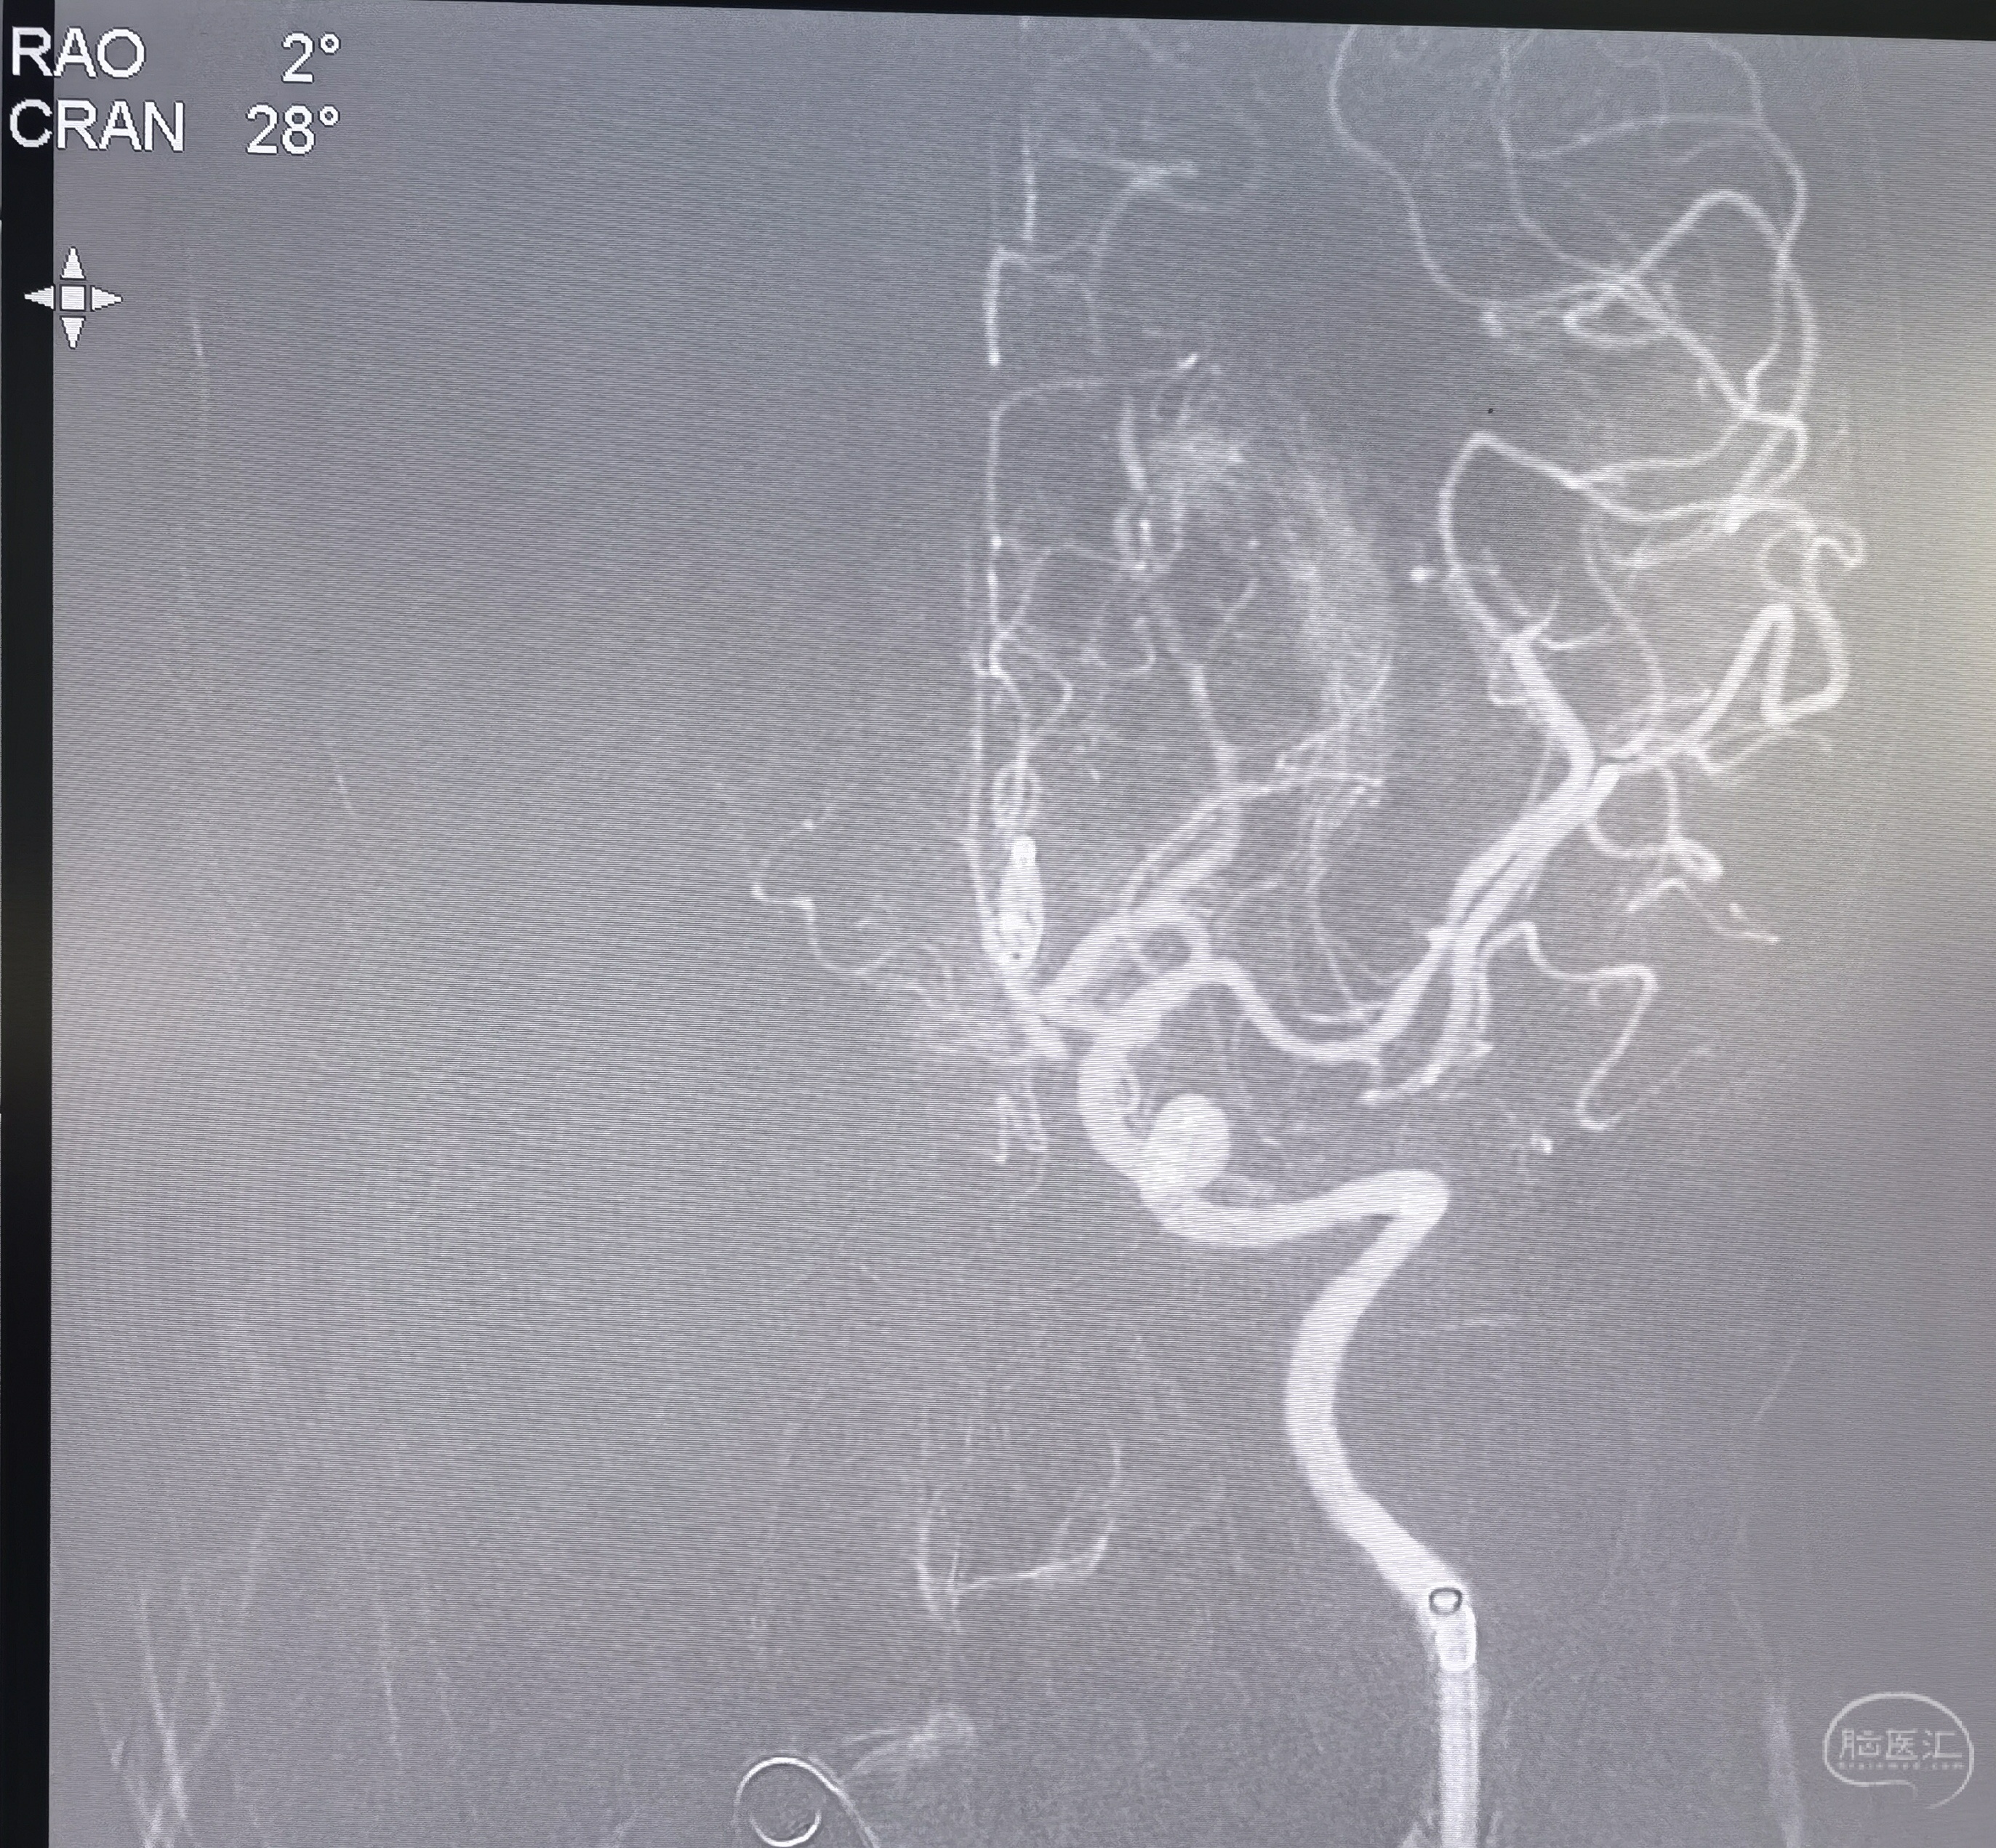

颈内动脉闭塞,微导丝超选通过后拟球囊扩张

颈内动脉起始段球囊扩张后中间导管顺势通过。